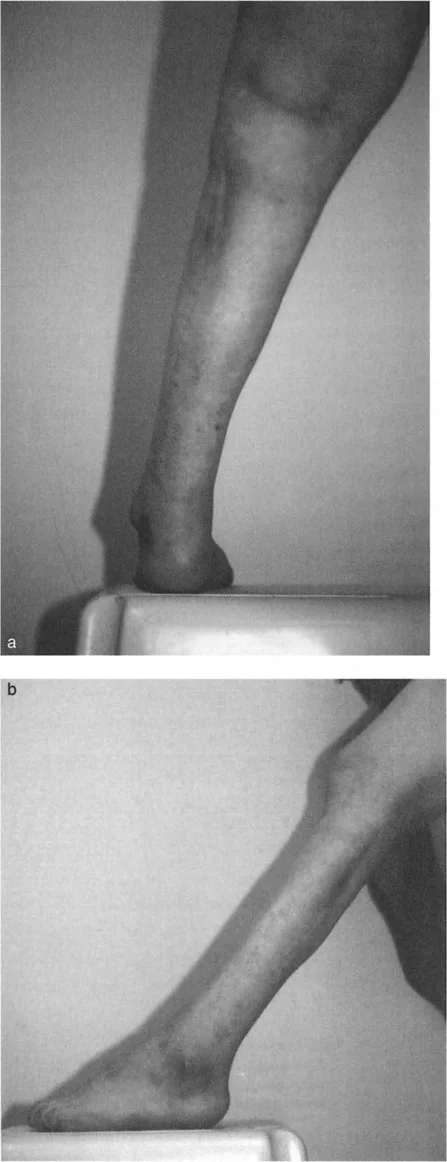

- صعوبة في المشي (العرج): يعتبر هذا من أبرز الأعراض، حيث يجد المريض صعوبة في وضع الكعب على الأرض بشكل طبيعي، مما يجعله يمشي على مقدمة القدم أو جانبها.

- محدودية حركة الكاحل: عدم القدرة على ثني القدم للأعلى (Dorsiflexion) بشكل كامل أو طبيعي.

- تشوه واضح في شكل القدم أو الكاحل: قد يلاحظ المريض أو المحيطون به تغيرًا في شكل القدم، مثل ارتفاع القوس بشكل مفرط في حالة القدم الجوفاء، أو انحراف الكاحل.

- تقييم المشية (Gait Analysis): ملاحظة كيفية مشي المريض لتحديد أي أنماط مشية غير طبيعية أو عرج.

- قياس نطاق الحركة (Range of Motion): تقييم قدرة الكاحل والقدم على الثني للأعلى والأسفل، والقلب للداخل والخارج. يتم قياس زاوية الكاحل الظهرية الظنبوبية (ADTA) لتحديد درجة تقوس الكاحل.